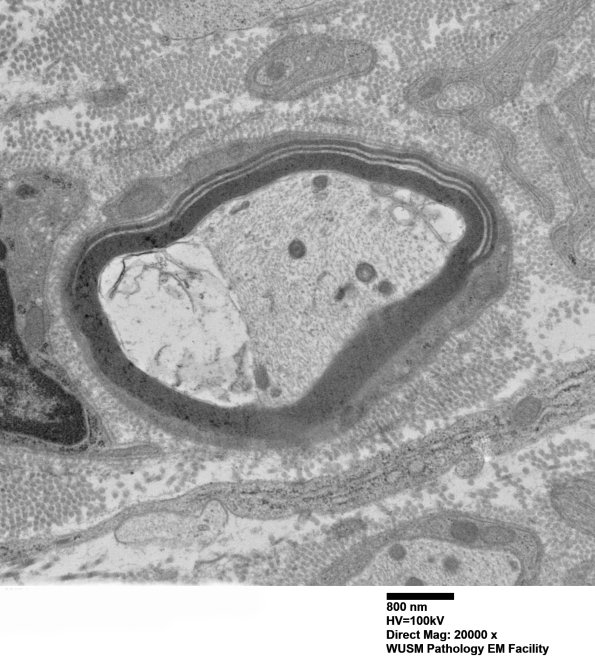

Washington University Experience | PERIPHERAL NEUROPATHY | 12 ANTI-MAG NEUROPATHY | 7C3A Anti-MAG (Case 7) sural_002 - Copy

7C3A Anti-MAG (Case 7) sural_002 - Copy

7C3A,B Note the junction with the intact myelin sheath. (electron micrographs)